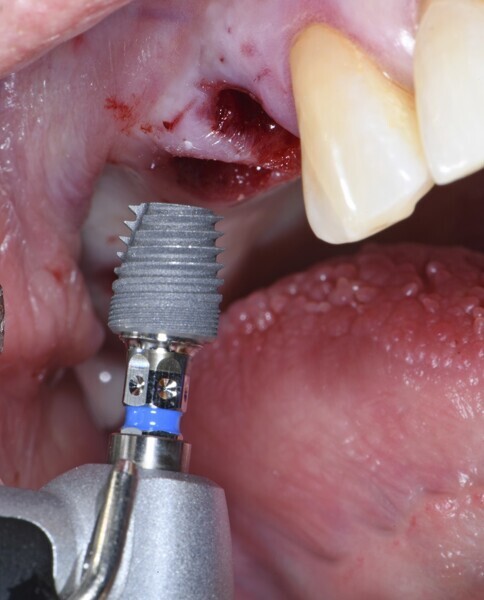

PrimeTaper EV implants (Dentsply Sirona) were placed in the maxillary premolar and molar positions (Fig. 2). MultiBase Abutments EV (Dentsply Sirona) were positioned and temporary screw-retained bridges loaded immediately (Figs. 3 & 4). To ensure that the implant positions were correct, a postoperative radiograph was performed (Fig. 5).